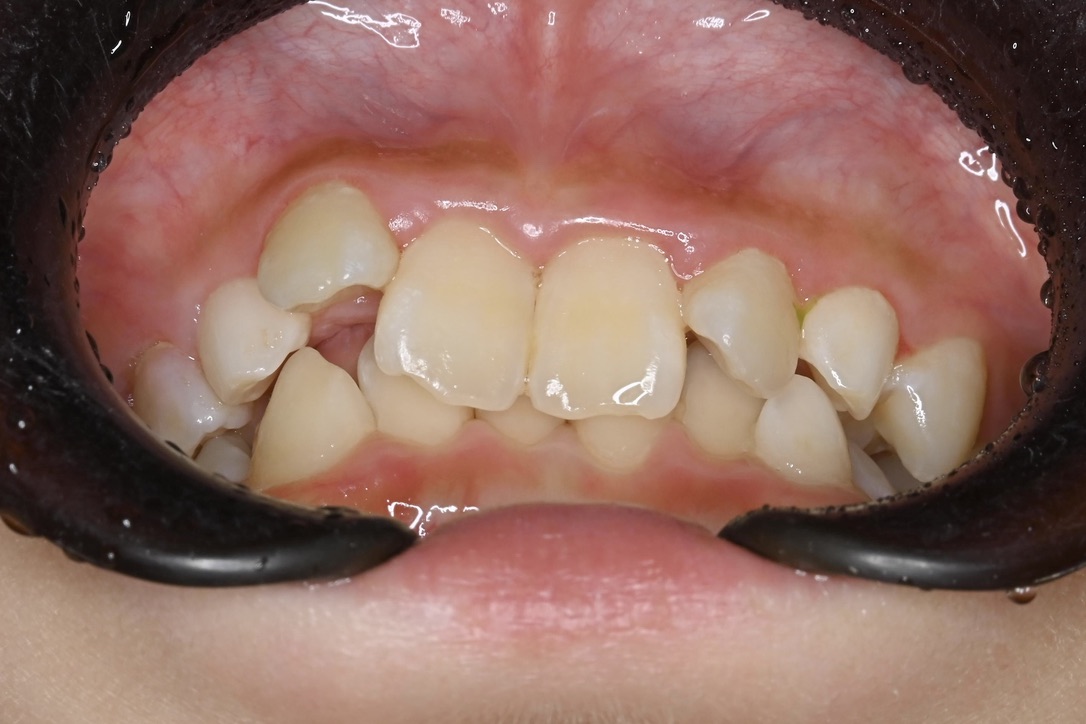

AFTER

主訴 通っている歯医者で矯正した方がいいと言われて気になっている。下の前歯がでこぼこしている。

診断名・主な症状 下顎前歯の叢生を伴う過蓋咬合

治療内容 上下の歯並びの幅を拡げつつ、前歯の関係を改善しました。

使用装置 急速拡大装置

リンガルアーチ

機能的矯正装置(マイオブレース)

抜歯部位 抜歯なし

治療期間 2年 + 後戻り止め期間(3年 )

通院回数 20回

費用 50万円程度(税別)  29331